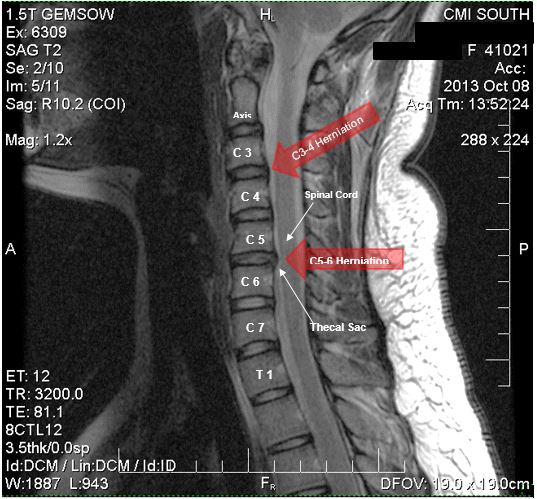

Протрузия диска с5 6 шейного отдела

Протрузия диска с5 6 шейного отдела 106 фотографий